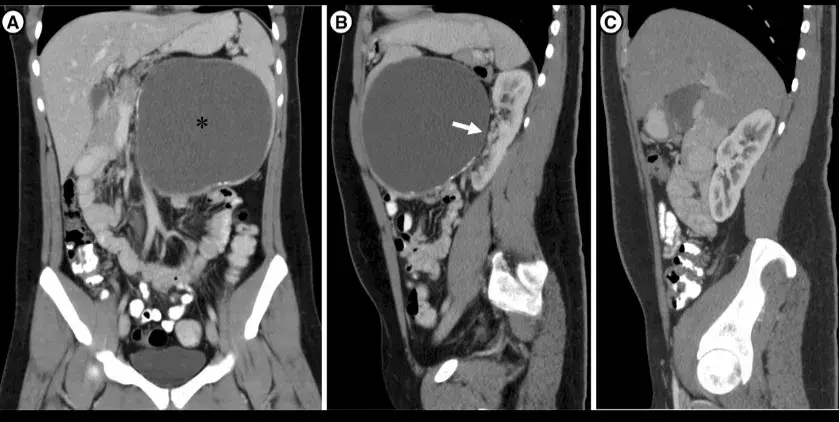

- Isquemia de circulação mesentérica (cólon, intestino delgado e estômago